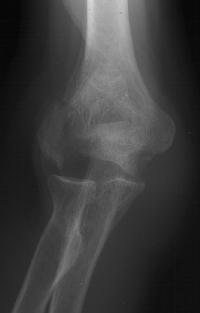

81 year old physically active woman sustained a left elbow fracture in a syncope related fall.

Lateral and central fracture component displacement.

Unusual contour visible at the medial metaphyseal flare.